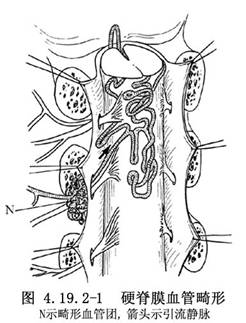

硬脊膜血管畸形亦稱硬脊膜動靜脈畸形(spinal dural AVMs),目前,多稱爲硬脊膜動靜脈瘻(spinal dural arteriovenous fistulae)。由於選擇性脊髓血管造影的開展和顯微手術的應用,對本病的發現率已明顯增加。畸形血管中含有供血動脈和引流靜脈,以及動靜脈之間的異常分流,亦可有畸形血管團。脊髓功能障礙症狀的產生,主要是脊髓的迴流靜脈內有動脈血的注入,使迴流靜脈內的壓力不斷升高所致。Symon(1984)報告的78例椎管內AVM中有55例位於硬脊膜或與硬脊膜表面有連屬。Rosenblum(1987)報告的81例中,硬脊膜AVM佔33%。其與硬脊膜內或脊髓AVM的不同點是:①本病好發於高齡病人,平均年齡爲59歲;②是後天性疾病;③多以疼痛和進行性癱瘓爲首發症狀,極少發生出血;④供血動脈均來自肋間動脈或腰動脈的硬脊膜分支;⑤病竈多位於椎間孔區,畸形血管團或動靜脈瘻埋置在覆蓋神經根及其附近的硬脊膜中,可有增粗且動脈化的引流靜脈穿過硬脊膜,紆曲走行於脊髓表面,與脊髓冠狀靜脈及靜脈叢相連屬(圖4.19.2-1);⑥手術比脊髓AVM簡單,只要將動靜脈間的分流阻斷或將病竈局部切除即可獲得良好效果,不必廣泛切除引流靜脈。供血動脈的人工栓塞術效果也較好(圖4.19.2-2,4.19.2-3)。